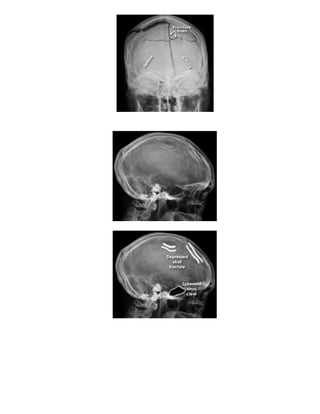

Vôùi voøm soï : Quan saùt caùc ñöôøng nöùt. Coù 3 loaïi ñöông nöùt.

Thöù nhaát laø gaõy ñöôøng ( linear ) loaïi naøy hay gaëp vaø thöôøng khoâng coù bieán chöùng.

Loaïi gaõy luùn ( Depress fracture ) loaïi naøy hay coù söï thoâng thöông cuûa chuû moâ naõo vôùi

beân ngoaøi , khi nghi ngôø phaûi laøm Ctscanner vaø phaãu thuaät ngay.

Gaõy hình sao ( Stellate ) deã phaùt hieän.

Keát luaän : caàn phaân bieät giöõa ñöôøng gaõy – khe khôùp – maïch maùu

Ñöôøng gaõy : Thaáu quang – Hình thaúng – Khoâng theo vò trí giaûi phaãu – Coù theå chaïy baét

ngang khe khôùp.

Maïch maùu : Ít thaáu quang – Chaïy töø trung taâm ra ngoaïi bieân.